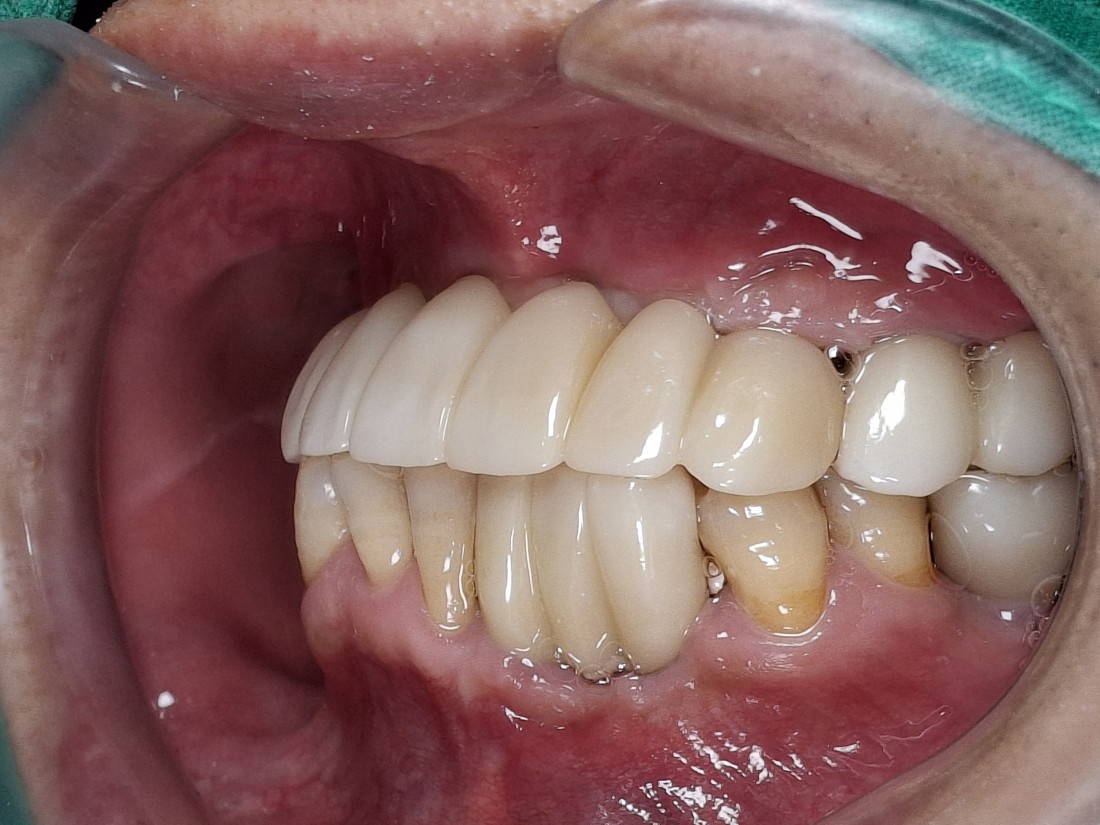

전남광주 임플란트 치과에서는

디지털가이드 임플란트 수술방법으로

한 번에 8개 이상의 임플란트를

심을 수 있습니다.

위, 아래 전체 임플란트를

단 두 번의 수술만으로 완성할 수 있어

임플란트 치과에 자주 내원하지 않으셔도 되고,

붓기 / 출혈 / 통증도 적기 때문에

빠른 회복을 기대할 수 있습니다.